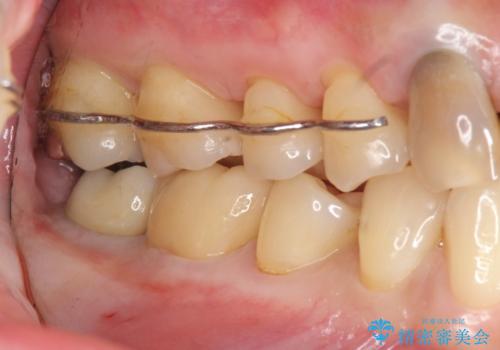

- 右下奥歯がグラグラし、噛めないことの改善を希望され来院されました。

X線写真より根尖付近までの骨吸収を認めます。

抜歯を余儀なくされる状況ですが、将来的にインプラントによる咬合機能回復を希望されたので抜歯と同時に骨補填剤を填入し骨の造成をしたのちのインプラント治療を計画します。